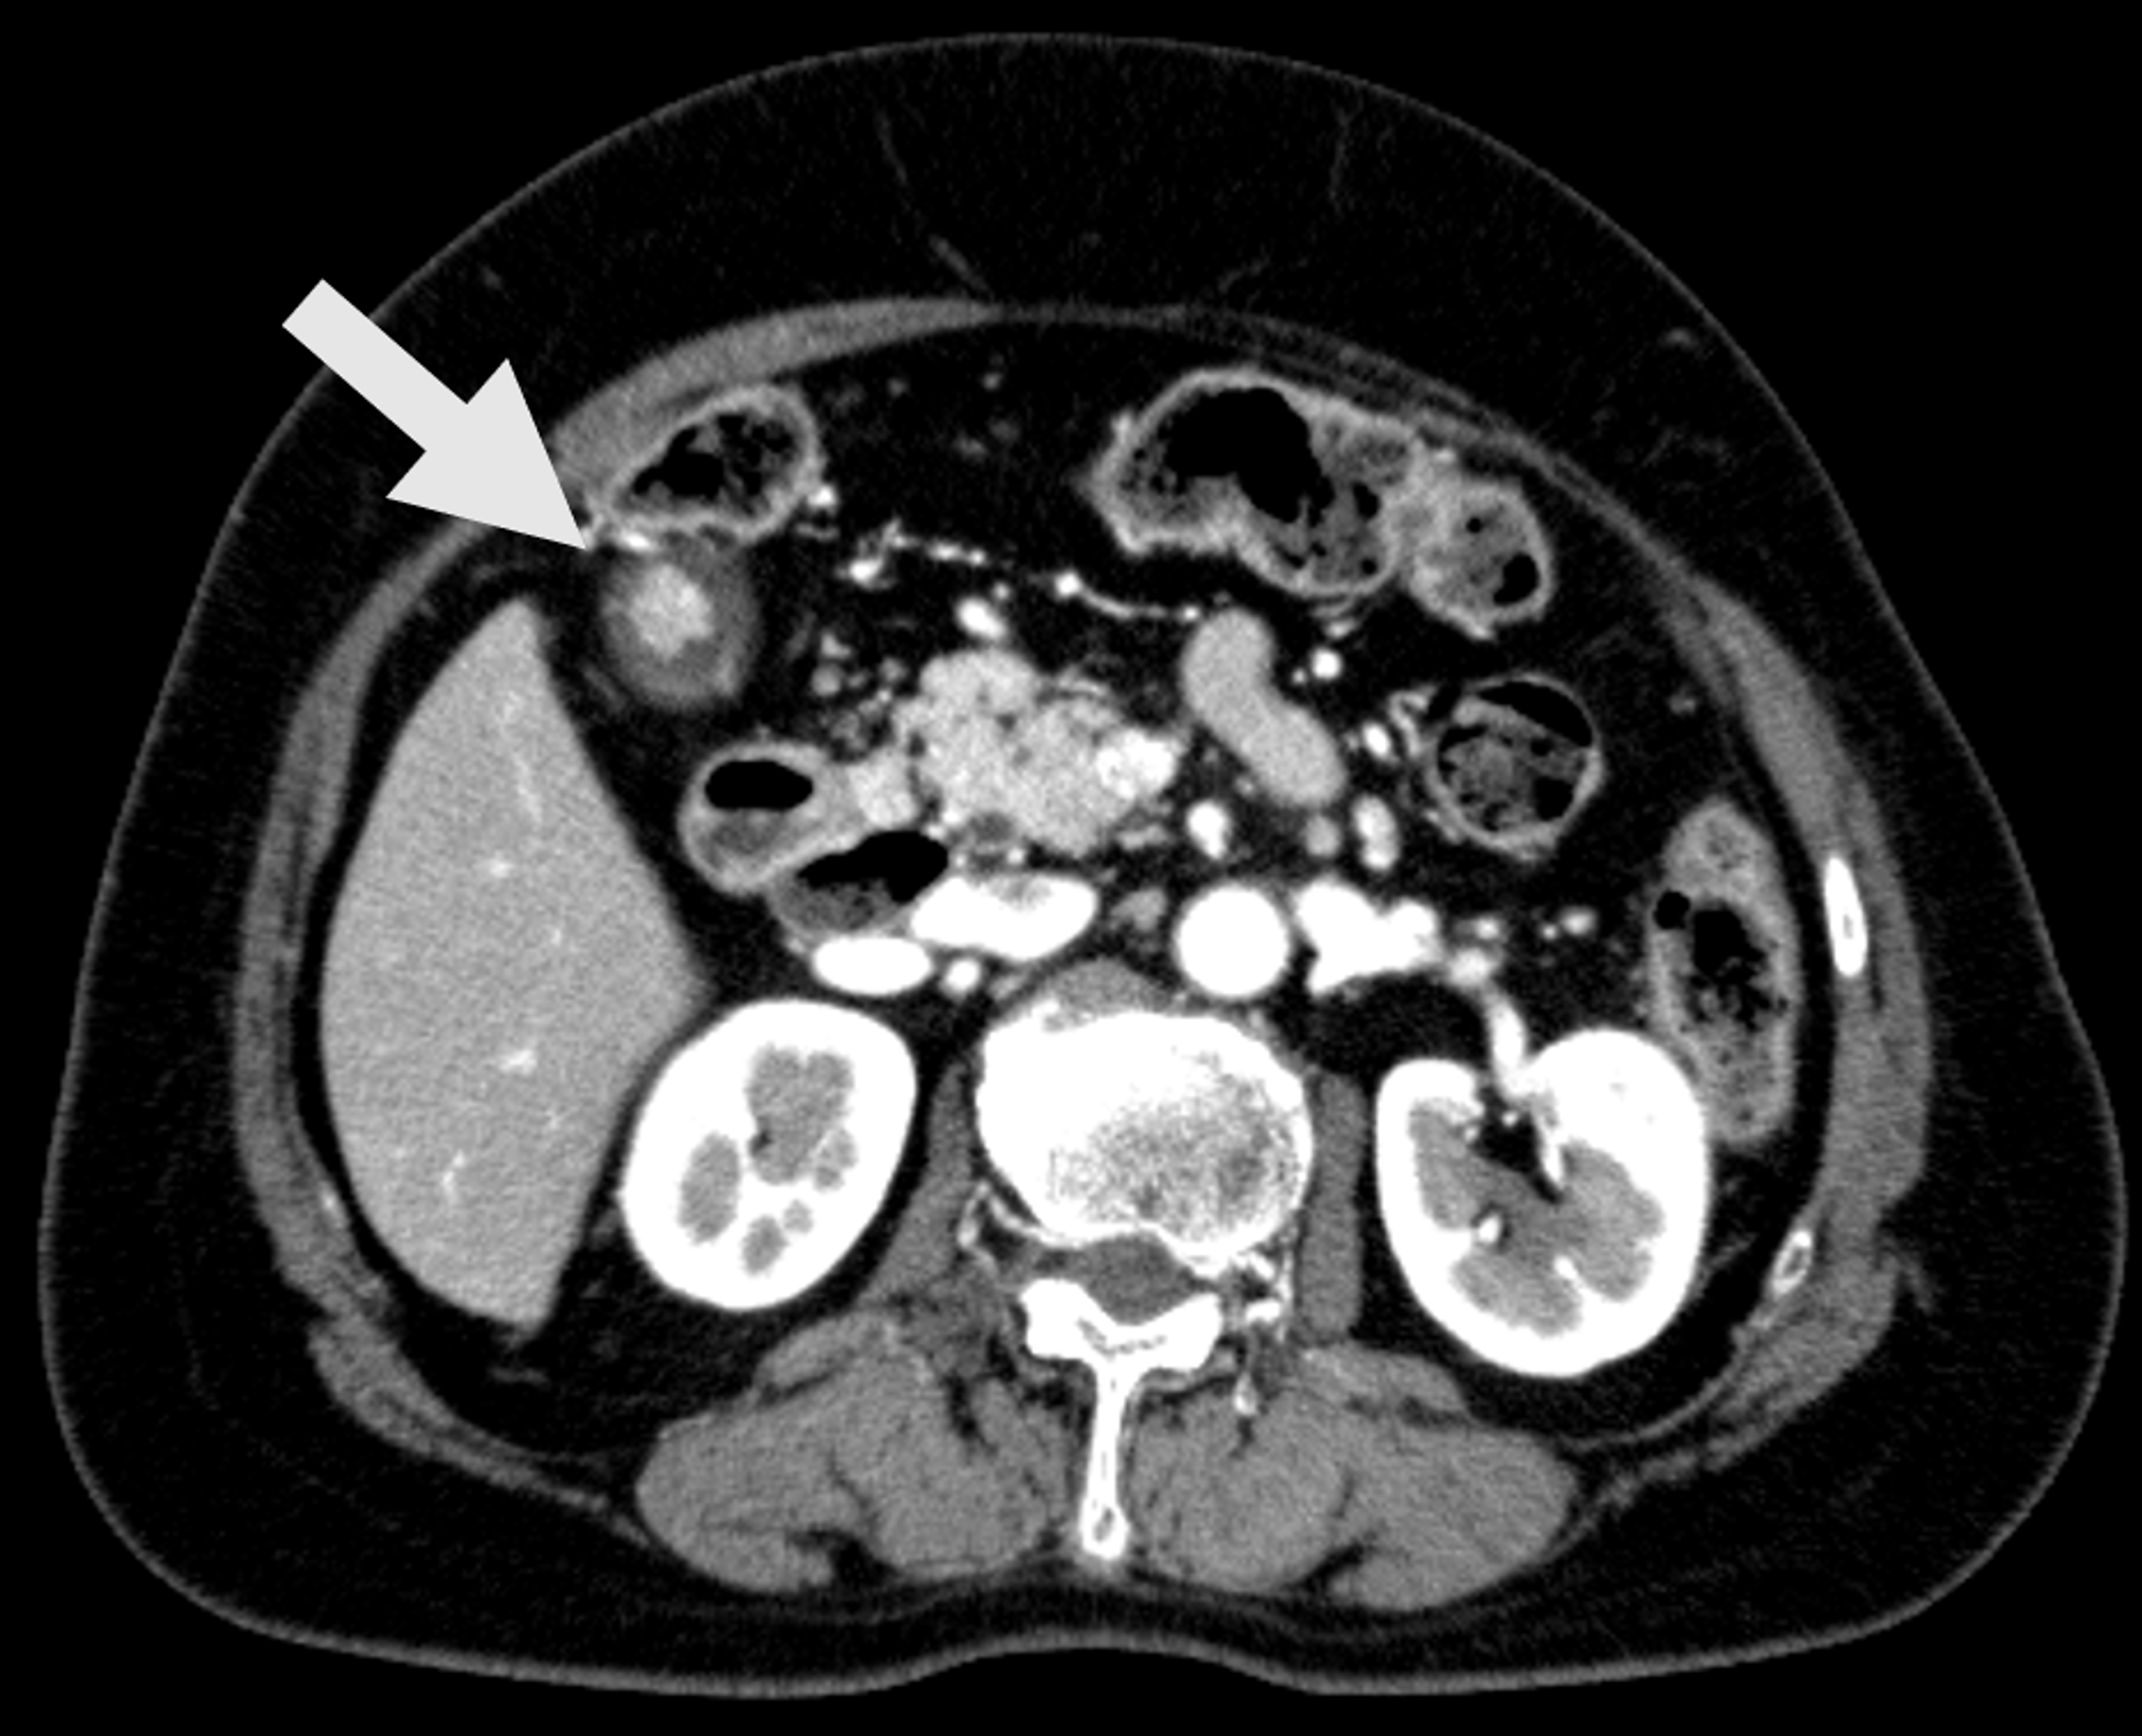

From www.currentsurgery.org

Gallstone Ileus Presenting With Cholelith Emesis and an Incidental Cholesterol Gallstone Radiology Ultrasound is by far the most common and useful imaging modality in assessing. On plain radiographs, gallstones typically appear as single or multiple, pyramidal, faceted, or cuboidal calcifications located in the right upper quadrant (ruq). The imaging signs of pneumobilia, an ectopic gallstone, and bowel obstruction constitute the rigler triad [2] (figs. Gallbladder wall cholesterolosis is a type of cholecystosis,. Cholesterol Gallstone Radiology.